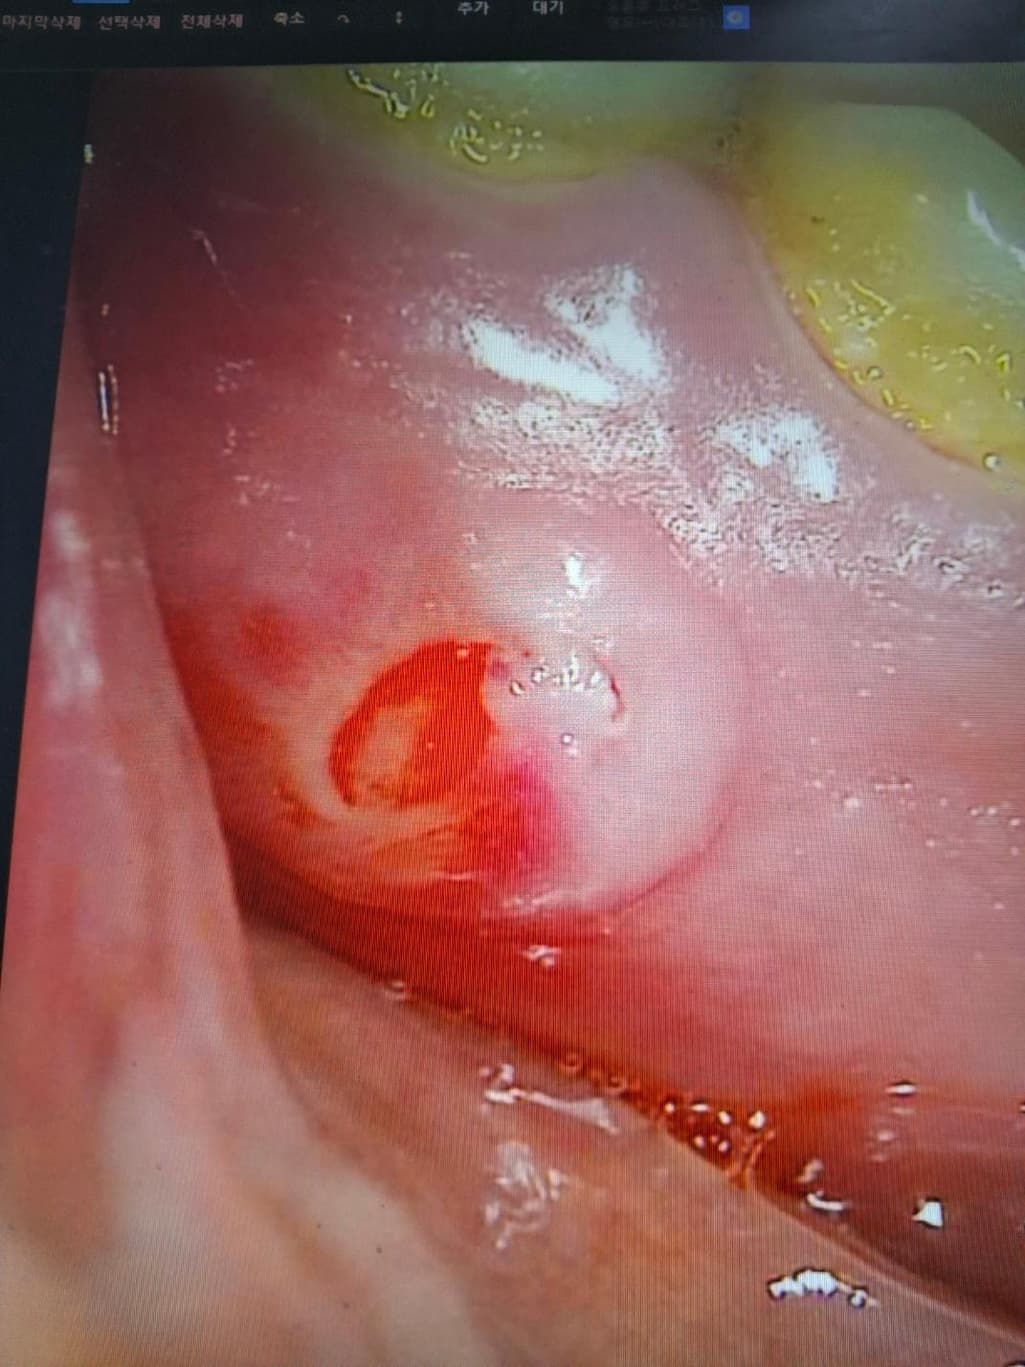

두달전(25년7월2일정도) 엄청 심한 염증을 앓고 난 후 두 주전까지 고생하다(25년8월 20일쯤) 간신히 붙어 있던 구강 점막이 (과일을 먹어서 그런것 같아요) 벗겨지면서 뼈가 노출이 되었는데 이 뼈가 부골인지 아닌지 점막은 재생이 되는 지 안 되는지 안 된다면 어떻게 해야 하는 지 궁금합니다. 단거 짠거 뜨거운거 먹으면 고통이 7에 달하고 평상시는 고통이 2정도 됩니다. 제가 항암한지 2년이 되어서 점막재생이 잘 안된다고는 하고 대학병원에서 진료 받았으나 구강암은 아니고 일단은 영양제 잔뜩 처방해 주면서 그렇게 있다가 3달 뒤에 보자고 하는 데 밥 먹을 때 넘 힘들고 이렇게 고통 속에 살 수는 없어서 어떻게 해야하는지 의견을 묻고 싶습니다.

• 1번 째 사진

잇몸을 이식하거나 하는 방법도 있으나 사진상으로는 염증만 줄어들면 괜찮을 것 같기도 합니다.

사진에 보이는 부분이 만져서 딱딱한 부분이 느껴진다면 부골일 가능성이 잇고 말랑하거나 딱딱한게 없다면 단순 염증일 가능성이 높습니다.